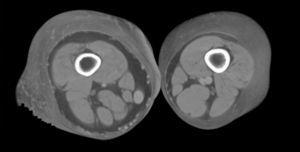

Hoy en día la utilización de los nuevos equipos TC multicorona y RM permiten la adquisición de imágenes con gran rapidez, pudiendo realizar reconstrucciones multiplanares de gran calidad, así como estudios angiográficos no invasivos13,23. Recientemente hemos estudiado 16 pacientes con síndrome de Klippel-Trenaunay mediante una venografía tomografía computarizada multicorte (TCM) o una venografía resonancia magnética tridimensional (RM-3D), utilizando imágenes axiales convencionales, reconstrucciones multiplanares (RMP), proyecciones de máxima intensidad (PMI) e imágenes tridimensionales (figs. 1-3). Las imágenes axiales convencionales fueron de utilidad para evaluar el tejido blando y el hueso y permitieron localizar el sistema venoso profundo y los vasos anómalos superficiales, determinando su relación con estructuras adyacentes. Las imágenes axiales, RMP y PMI fueron empleadas para trazar el origen, trayecto y extensión de las malformaciones venosas. Las imágenes de la superficie cutánea permitieron evaluar la localización y la extensión de la mancha en vino de Oporto y demostrar la hipertrofia de la extremidad. Las reconstrucciones tridimensionales permitieron demostrar las varicosidades y el origen y trayectoria de los vasos aberrantes (figs. 4 y 5). Ninguno de los pacientes requirió otra técnica complementaria invasiva (flebografía convencional) para confirmar el diagnóstico y planificar las estrategia terapéutica24.

Figura 4. Agenesia de la vena poplítea en paciente con síndrome de Klippel-Trenaunay.

Figura 5. Hipertrofia músculo-esquelética e hipoplasia de vena femoral superficial en paciente con síndrome de Klippel-Trenaunay.